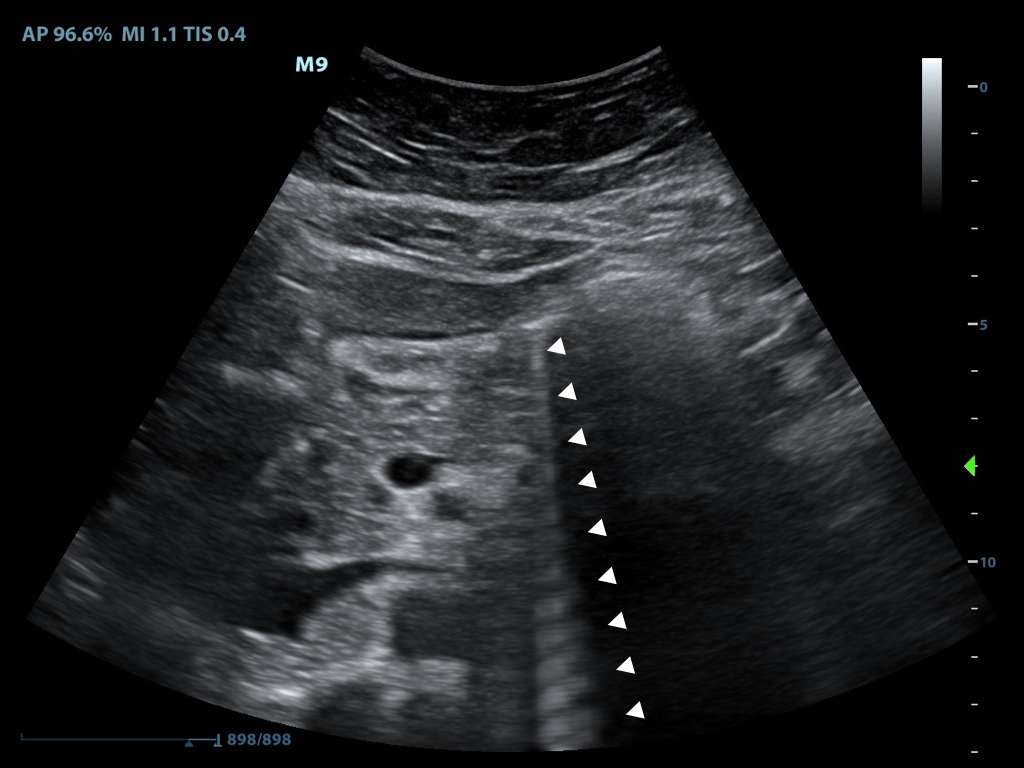

- B-mode or ‘brightness mode’ provides structural information utilizing different shades of gray (or different ‘brightness’) in a two-dimensional image (Figure 1)

- Figure 1. B-Mode image of free fluid in the right upper quadrant

- Brightness is determined by the amplitude of returning echoes

- Anechoic/Echolucent – Complete or near absence of returning sound waves, area is black

- Hypoechoic - Structure has very few echoes and appears darker than surrounding tissue

- Hyperechoic/Echogenic – Large amplitude of returning echoes appears brighter than surrounding tissue